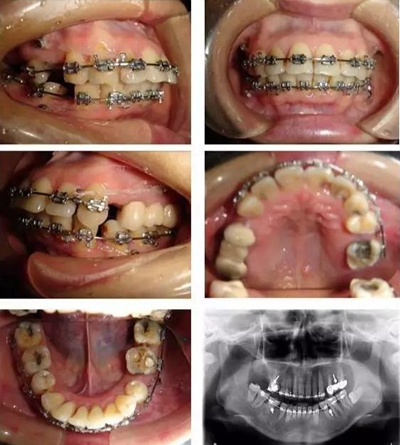

▲ 圖3 矯治中,利用微種植體支抗內(nèi)收前牙時(shí)的牙(牙合)像及曲面斷層片